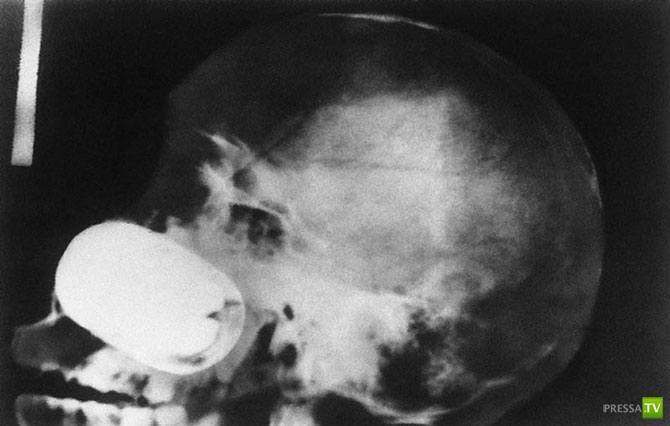

Череп человека, которому в голову выстрелили пневматическим молотком.